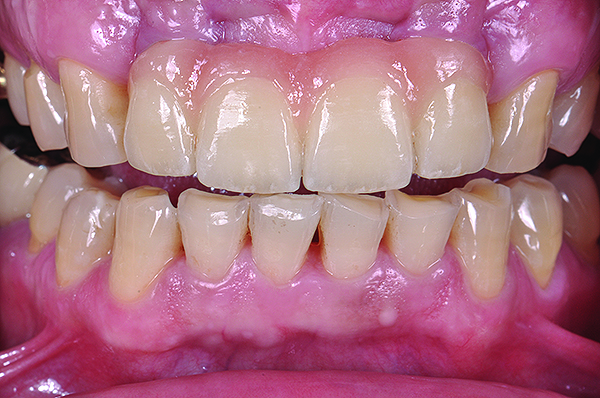

Class I (CL-I) powder and liquid porcelains are created from materials primarily containing silicon dioxide and possess a glassy matrix and varying amounts of a crystalline phase within the glassy matrix (eg, Creation Porcelain, Jensen Dental, www.jensendental.com; Ceramco 3, DENTSPLY International, www.dentsply.com; EX-3, Kuraray Noritake Dental, Inc, www.kuraraynoritake.com). The CL-1 group includes feldspathic porcelains, referred to as such because they were originally—and some continue to be—made from naturally occurring feldspars (ie, aluminosilicates composed of assorted quantities of potassium, sodium, barium, or calcium).9,17 Several feldspathic material options are available on the market today (eg, VITA VM 13, VITA Zahnfabrik, www.vita-zahnfabrik.com; Vintage Halo, Shofu, www.shofu.com) (Figure 1 through Figure 3).

CL-I materials are fabricated by hand (Figure 4); they are the most conservative and generally the most translucent ceramic materials, but they are also the weakest.9,10,18 The material’s high translucency and esthetics create the illusion of natural teeth.9 Powder/liquid porcelain materials are ideal for cases in which significant enamel remains and/or there is healthy tooth structure on the teeth (ie, 50% or more remaining enamel on the tooth, 50% or more of the bonded substrate is enamel, and 70% or more of the margin is in the enamel). Feldspathic porcelain restorations that are bonded to primarily enamel substrates have proven to be highly successful long term.19

Powder/liquid porcelains demonstrate high esthetics and workability, and because they can be layered very thinly and placed directly on the enamel, they are considered the most conservative of the metal-free ceramic classes.10 CL-I porcelains require a thickness of 0.2 mm to 0.3 mm for each shade change.20,21

This class of materials is generally indicated for anterior restorations, but can also be used for the occasional bicuspid and rare molar, providing all parameters are at a very low risk level (Figure 5 and Figure 6).

Figure 1 Preoperative, preparation, and final postoperative images of a 2-unit CL-I feldspathic veneer case.

Figure 1

Figure 2 Preoperative, preparation, and final postoperative images of a 2-unit CL-I feldspathic veneer case.

Figure 2

Figure 3 Preoperative, preparation, and final postoperative images of a 2-unit CL-I feldspathic veneer case.

Figure 3